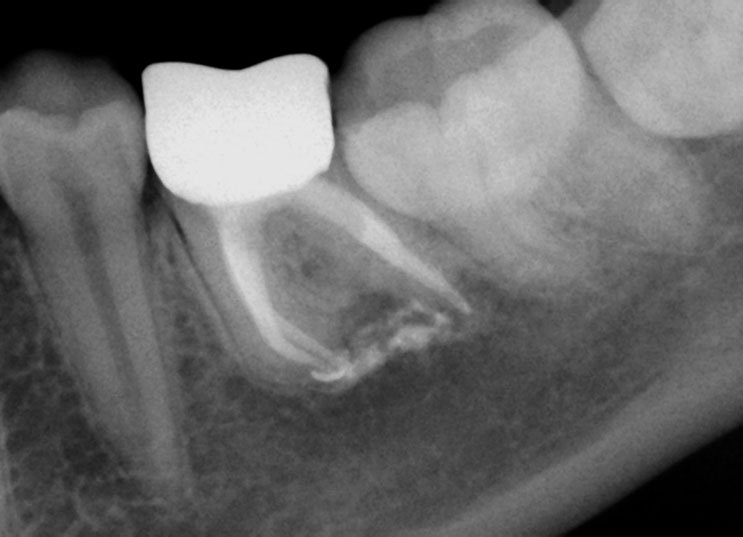

Pre-op

Pain in mandibular first molar after endo. Previous dentist unable to locate mesial canals. Obturated only the distal canal. Patient has generalized periodontal problems as well.

Red arrows show the two “white spots” indicating the calcified mesial canals.

Missed second distal canal (red arrow)

Pre-op & Post-op